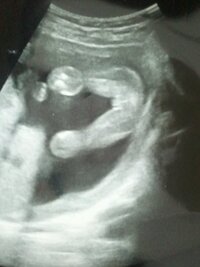

エコー 白い三本線 エコー写真 性別の見分け方 男の子女の子別エコー 妊娠週まとめてみました ママびよりウェブ 24w3のエコーです 三本線がわりとしっかり写っているように見えるの Yahoo 知恵袋 女の子のエコー写真の特徴2:三本線 女の子のエコー写真の特徴2つめは、三本線です。女の子の場合は、股の割れ目と大陰唇で見分けることができます。 この割れ目が女の子の外性器です。 三本線やコーヒー豆などと表現されることもあります。 男の子の場合、見分ける方法は「男の子のシンボル」が一番とされています。 足の間に突起物の様なシンボル が見えれば、男の子と判断される事が多い様ですね。 大変分かりやすい判別方法なので、比較的早い時期でも分かる事が多いとされています

これが 女の子の3本線 13週でエコーをとったのですが おし Yahoo 知恵袋

エコー写真になります これが女の子の証 3本線というものでしょうか Yahoo 知恵袋